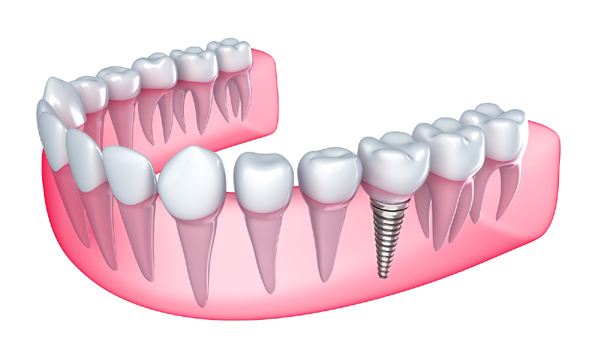

الفينير: ويشتهر أيضاً باسم قشرة الأسنان أو عدسات الأسنان وهي عبارة عن قشرة شفافة أو شبه شفافة شديدة الرقة في السمك لكنها قوية وصلبة ويتم صناعتها وتشكيلها وتحديدها بشكل خاص لكل فرد على حدى حيث تركب على الأسنان الحقيقية لتصنع ابتسامة هوليود الدائمة, كما يمتاز الفينير بأنه يسبب أقل الحلول ضرراً على الأسنان مقارنة بأنواع عدسات ابتسامة هوليود وطرابيش الأسنان الأخرى المختلفة, وينقسم الفينير لنوعين:

إن الحصول على ابتسامة هوليوود وتركيب القشور قد لا يشمل جميع الأسنان، وقد يكتفي الطبيب بتركيب هذه القشور على الأسنان الامامية فقط أو تلك الأسنان التي تعاني من المشاكل المذكورة سابقاً.

إن تحضير الأسنان لوضع القشور عليها يتضمن إزالة 0.5 ملم من مينا سطح السن، وهو ما يقارب سماكة القشور التي ستوضع على السن.

من ثم يقوم الطبيب بعمل نموذج للقشور عن طريق ارسالها إلى المختبر، هذه العملية تستغرق 1- 2 أسبوعاً تقريباً.

3- التجربة والإنتهاء

قبل الوضع النهائي للقشور، سيقوم الطبيب بوضعها على اسنان المريض للتاكد من اللون والحجم، إذ سيكون بإمكانه تهذيب القشور وفق المطلوب إن لم تكن مناسبة.

بعد التاكد من ذلك سيتم تنظيف الاسنان لتركيب القشور بشكل نهائي باستخدام لاصق مخصص، من ثم يقوم الطبيب بوضع موجات من الضوء مخصصة لتثبيت اسنان هوليود سمايل.